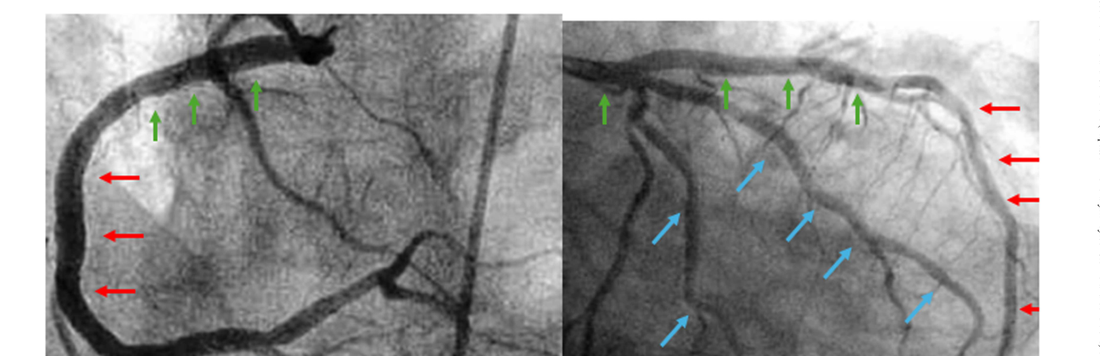

Figure 4. Fluoroscopic angles to find the ZOV. Vertical segments (mid RCA, m-distal LAD) use LAO and RAO (red arrows). Horizontal segments (LMS, pLAD, p-d RCA) use LAO cranial and LAO caudal (green arrows). Diagonal segments (PLV, LCx) use RAO caudal and LAO cranial (blue arrows). Source: Wu et al., Catheter Cardiovasc Interv 2026, CC BY.Figure 7. (a) Near side miss: pull the wire and microcatheter back so that the wire travels a longer distance toward the target. (b) Far side overshoot: pull back to the center of the cap and rotate 180 degrees, then re-puncture. Source: Wu et al., Catheter Cardiovasc Interv 2026, CC BY.

Figura 4. Ângulos fluoroscópicos para achar a ZOV. Segmentos verticais (CD média, DA média/distal) usam OAE e OAD (setas vermelhas). Horizontais (TCE, DA proximal, CD proximal/distal) usam OAE cranial e OAE caudal (setas verdes). Diagonais (VPL, Cx) usam OAD caudal e OAE cranial (setas azuis). Fonte: Wu et al., Catheter Cardiovasc Interv 2026, CC BY.Figura 7. (a) Near side miss: recuar fio e microcateter para que o fio percorra distância maior até o alvo. (b) Far side overshoot: recuar para o centro da capa, rotacionar 180 graus e repuncionar. Fonte: Wu et al., Catheter Cardiovasc Interv 2026, CC BY.

Figura 4. Ángulos fluoroscópicos para hallar la ZOV. Segmentos verticales (CD media, DA media/distal) usan OAI y OAD (flechas rojas). Horizontales (TCI, DA proximal, CD proximal/distal) usan OAI craneal y OAI caudal (flechas verdes). Diagonales (PLV, Cx) usan OAD caudal y OAI craneal (flechas azules). Fuente: Wu et al., Catheter Cardiovasc Interv 2026, CC BY.Figura 7. (a) Near side miss: retirar alambre y microcatéter para que el alambre recorra mayor distancia hacia el blanco. (b) Far side overshoot: retirar al centro de la capa, rotar 180 grados y repuncionar. Fuente: Wu et al., Catheter Cardiovasc Interv 2026, CC BY.